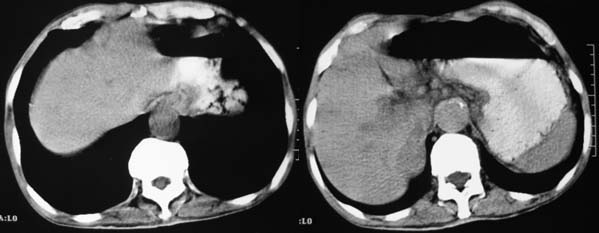

上腹部横断图象显示:心包,胃体小弯侧,肾等器官周围以及肠系膜腹膜后多发的大小不等的小结节样软组织密度影,部分境界不清,未见明显钙化.如此广泛的小结节样影,我认为首先考虑淋巴结肿大.能够引起淋巴结肿大的最常见的原因为:1.炎症(结核常见);2.转移;3.淋巴瘤.其中淋巴结结核不同程度可见钙化,而且这么大范围少见,暂不考虑.

右侧肾上腺区可见软组织密度肿块,密度欠均匀,未见钙化;右肾下极内侧可见实质局限性增厚并呈肿块样突出肾轮廓.

肝胃间隙,双侧肾周间隙,腹主动脉旁类圆形软组织结节影,首先考虑是增大的淋巴结。

从平扫看:左肾上腺区域见软组织结节,内见钙化。

右侧肾上腺区软组织肿块影,密度不均,其周围及腹主动脉周围,心包周围均见多个淋巴结肿大.结合临床首先考虑:右肾上腺恶性肿瘤伴腹腔内及心包淋巴结转移.